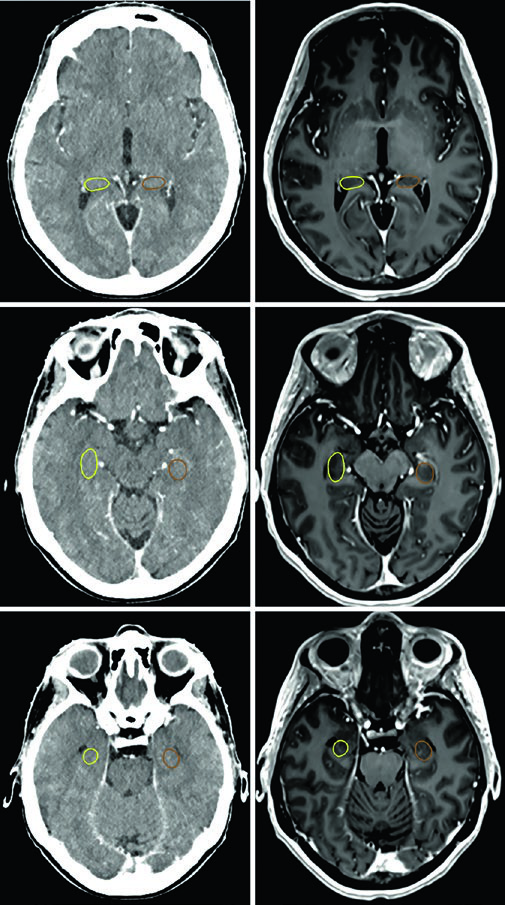

Las imágenes axiales de TC se adquieren con espesor de corte de 1 mm para SRS, FSRT y protonterapia, o 2 mm para 3D-CRT, IMRT y VMAT, cubriendo toda la cabeza hasta el nivel de los hombros. El co-registro con RM diagnóstica es altamente recomendado — secuencias T1 poscontraste o FLAIR para visualización tumoral, y T1 nativo o 3D T2/CISS para delinear nervios craneales e hipocampo. Se emplea contraste IV salvo contraindicación.

Cada OAR tiene una ventana de visualización óptima. El tronco encefálico, quiasma óptico y componentes intracraneales de los nervios ópticos se ven mejor en ventana cerebral. Los nervios ópticos en los canales ópticos y sus componentes orbitarios son más nítidos en ventana de partes blandas. Las cócleas solo se identifican con precisión en ventana ósea — y según la posición de la cabeza, pueden no encontrarse en el mismo corte axial. El hipocampo — específicamente la zona subgranular — se delinea en T1 de RM y se visualiza como sustancia gris hipointensa, desde el nivel donde limita con el atrio del ventrículo lateral superiormente hasta la extensión inferior del cuerno temporal.

El caso del oligodendroglioma de la Figura 29.5 muestra un paciente tras craneotomía frontotemporal izquierda con resección parcial que involucra la ínsula izquierda, porciones del opérculo y extensión hacia el centrum semiovale izquierdo. El GTV (rojo) abarca la enfermedad residual en FLAIR y la cavidad operatoria. La expansión de 1,0 cm genera el CTV (amarillo), con restricción anatómica fuera de la fosa posterior, cráneo y estructuras de línea media. El PTV (azul) recibe un margen adicional de 0,3 cm.